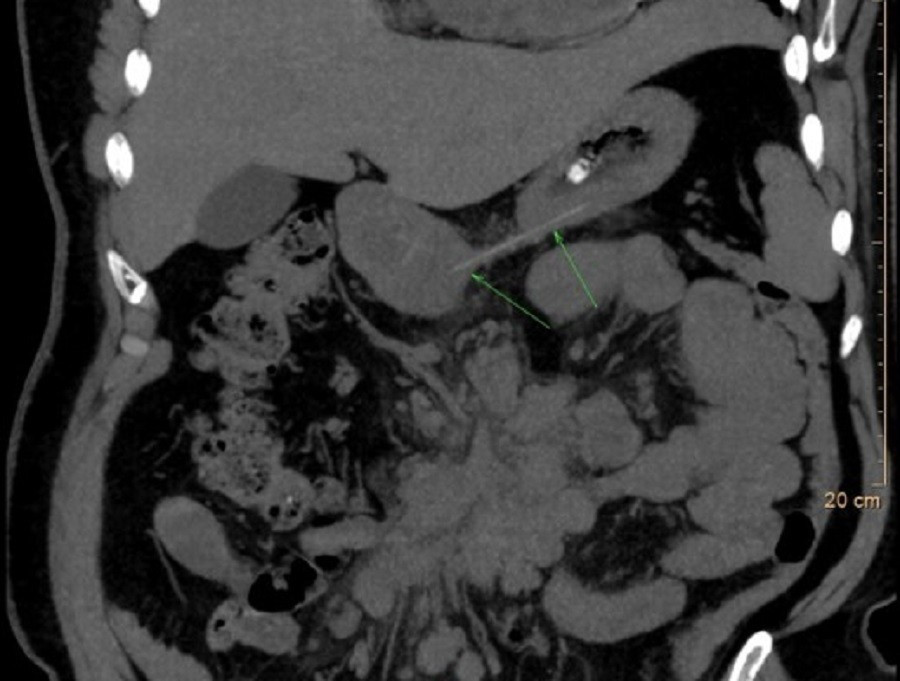

Chiếc xương cá (vị trí mũi tên) là thủ phạm khiến người bệnh phải nhập viện

Kết quả nội soi Tai Mũi Họng ghi nhận tình trạng phù nề nhiều ở vùng sụn phễu trái. Nội soi dạ dày – thực quản không phát hiện dị vật trong lòng ống tiêu hóa. Tuy nhiên, phim X-quang cổ nghiêng cho thấy hình ảnh nghi ngờ có dị vật. Để đánh giá chính xác, các bác sĩ chỉ định chụp CT và phát hiện một mảnh xương cá kích thước khoảng 1 x 22 mm đã xuyên ra khỏi đường tiêu hóa và cắm sâu vào thùy trái tuyến giáp.

Đây là tình huống nguy hiểm, có nguy cơ gây nhiễm trùng, áp-xe cổ hoặc tổn thương các cấu trúc quan trọng vùng cổ. Các bác sĩ thuộc ba chuyên khoa Tai Mũi Họng, Ngoại lồng ngực – mạch máu và Chẩn đoán hình ảnh đã nhanh chóng hội chẩn và quyết định phẫu thuật mở cổ để lấy dị vật. Song song đó, bệnh nhân được điều trị bằng kháng sinh, kháng viêm và thuốc giảm đau nhằm kiểm soát nhiễm trùng và giảm phù nề.